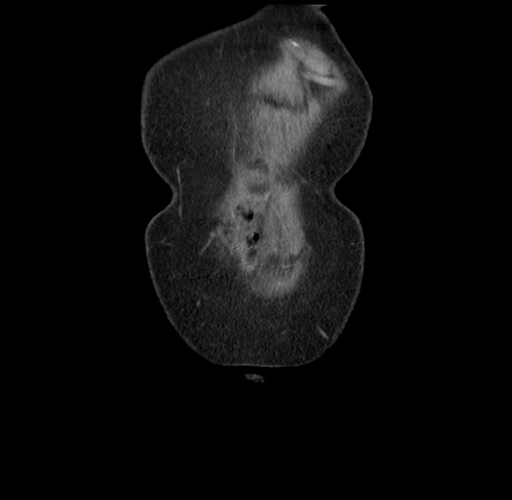

Pre-Chemo: Coronal Venous

Coronal Venous